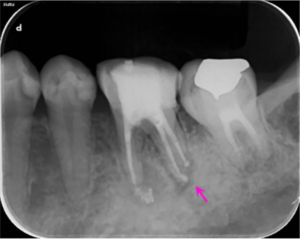

左図のレントゲン写真では根の先に炎症があり骨が溶けている部分があります(矢印部) 。

根の治療2か月後のレントゲン写真です。矢印の部分の骨の溶けている部分の大きさが小さくなっています。